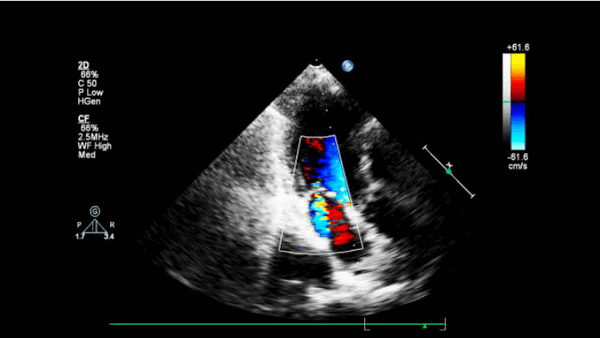

- Острый дефект межжелудочковой перегородки (ДМЖП). Эта патология часто происходит около верхушки сердца и чаще встречается при нижнем инфаркте левого и инфаркте правого желудочков. Нарушение непрерывности МЖП можно увидеть на 2-D эхокардиограмме в апикальной 4-камерной, парастернальной длинной оси и короткой оси. Цветное допплеровское картирование может точно показать дефект. Импульсно-волновой допплер, перемещенный вдоль правой стороны МЖП (парастернальная длинная ось или иногда четырехкамерная проекция), может показать турбулентную струю сброса.